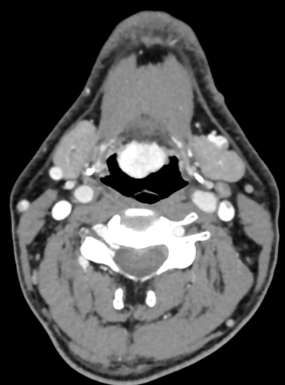

TORS approach to the parapharyngeal space is a minimal access surgical technique for diseases in this complex anatomical area. Learn more.